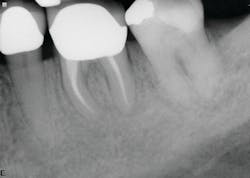

The second case involves a patient with tooth no. 19 having substantial furcation damage and moderate-sized apical periodontitis (figure 3).

Treatment included a two-visit approach, with two weeks in interim calcium hydroxide therapy.

Healing is noted on the six-month follow-up (figure 4).